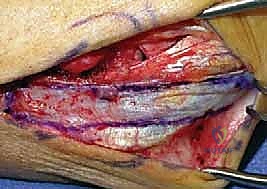

التدخل الجراحي: المعيار الذهبي

بالنسبة للغالبية العظمى من المرضى النشطين، والشباب، والرياضيين، تعتبر الجراحة هي الحل الجذري والوحيد لاستعادة استقرار الكوع ومنع التآكل الغضروفي المبكر (الخشونة). نظراً لأن الأربطة الممزقة بشكل مزمن تضمر وتفقد جودتها، فإن مجرد خياطتها (الإصلاح المباشر) غالباً ما يبوء بالفشل. لذلك، فإن الإجراء المفضل عالمياً والذي يبرع فيه الأستاذ الدكتور محمد هطيف هو إعادة بناء الرباط (Reconstruction) باستخدام رقعة وترية.